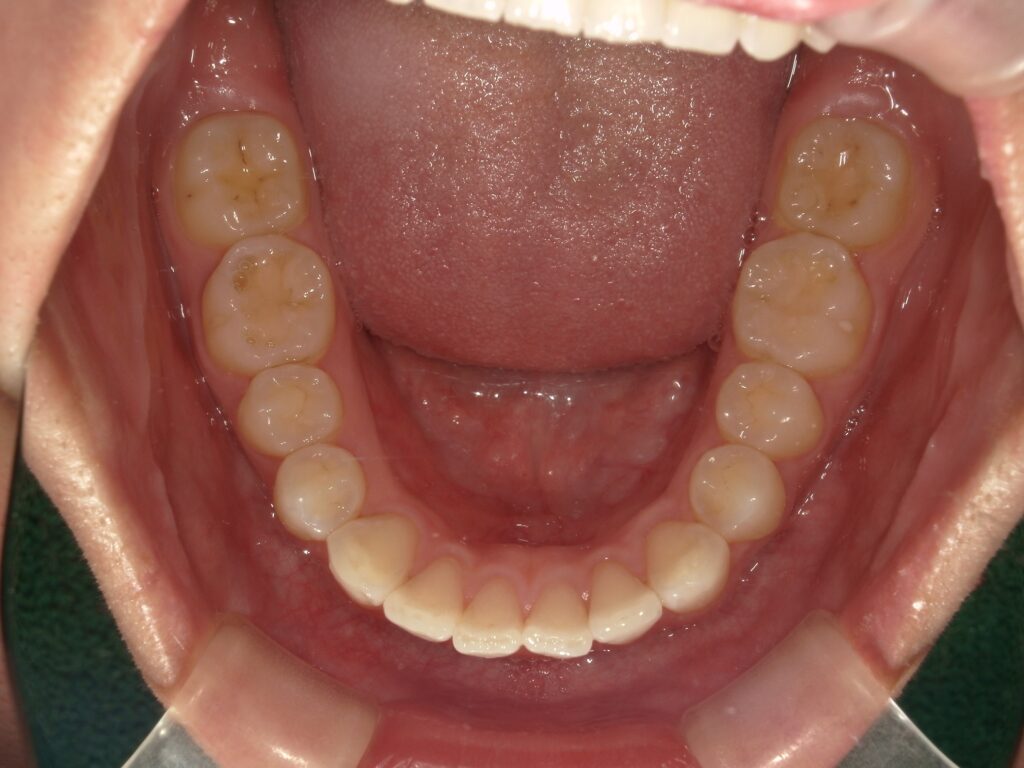

【治療後

部分矯正のメリットは治療期間が短いこと、そして費用が抑えられることです・

装置をつける期間も短いので、あまり目立つことなく治療を進めることができます。